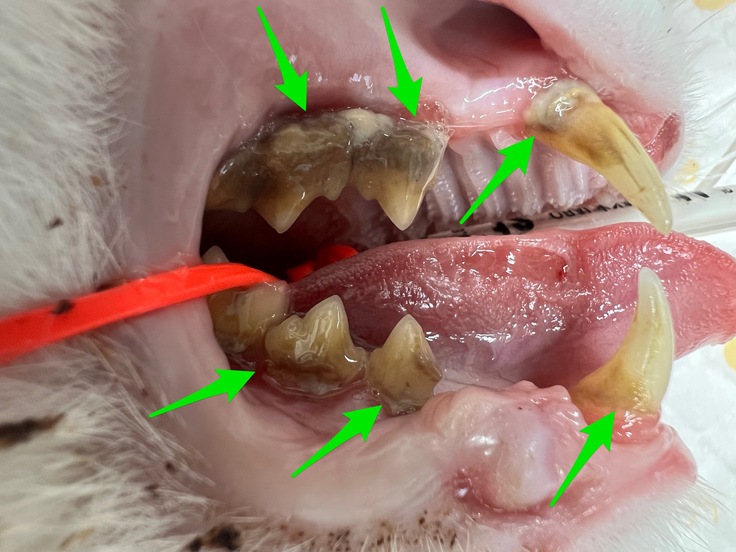

猫ちゃんの歯肉口内炎はどうしたらよいの?②治療法

|歯肉口内炎の治療方法は?

歯肉口内炎の治療の基本的な考えたとしては、原因の除去と炎症のコントロールです。

歯石や歯垢の付着が多い場合は、歯石除去(スケーリング)を行うことで、改善することもあります。

また、中程度〜重度である場合は、外科的処置を積極的に行います。全臼歯抜歯(犬歯以外の歯の抜歯)は、長期的に良好な結果となることが示されており、歯肉口内炎の70〜80%の猫で、大幅な改善もしくは治癒が報告されています。